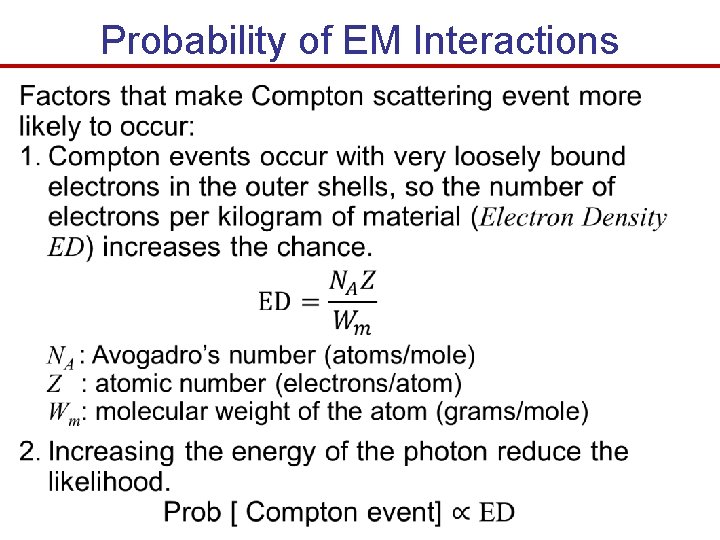

Probability of EM Interactions

Probability of EM Interactions

Tables